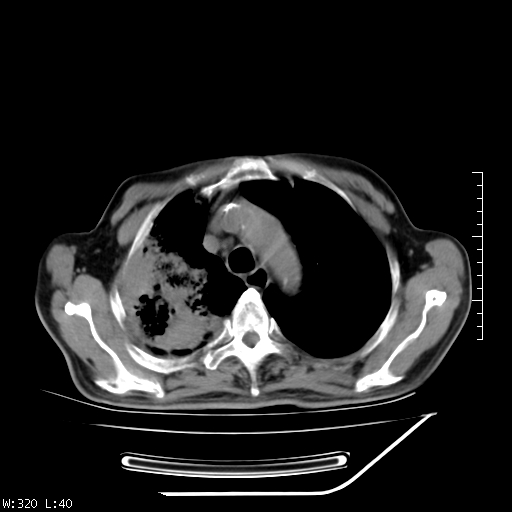

标题: CT23994:男、72、咳嗽、气短两月余,近来消瘦。 [打印本页]

标题: CT23994:男、72、咳嗽、气短两月余,近来消瘦。

右上肺实变,与胸膜关系密切,右肺容积缩小,隆突下淋巴结增大,考虑1 肺结核 2 肺癌

右上肺大片状密度增高影,与胸膜关系密切,内见低密度透亮影,胸膜下可见三角形不张影,左下肺沿支气管走形结节影,纵膈内淋巴结显示。考虑结核并疤痕性不张可能性大,建议穿刺活检,排除肺泡癌。